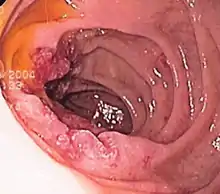

Endoscopic image of gastric antral vascular ectasia seen as a radial pattern around the pylorus before (top) and after (bottom) treatment with argon plasma coagulation Endoscopic image of Barrett's esophagus, which is the area of red mucosa projecting like a tongue.

Endoscopic image of Barrett's esophagus, which is the area of red mucosa projecting like a tongue. Deep gastric ulcer